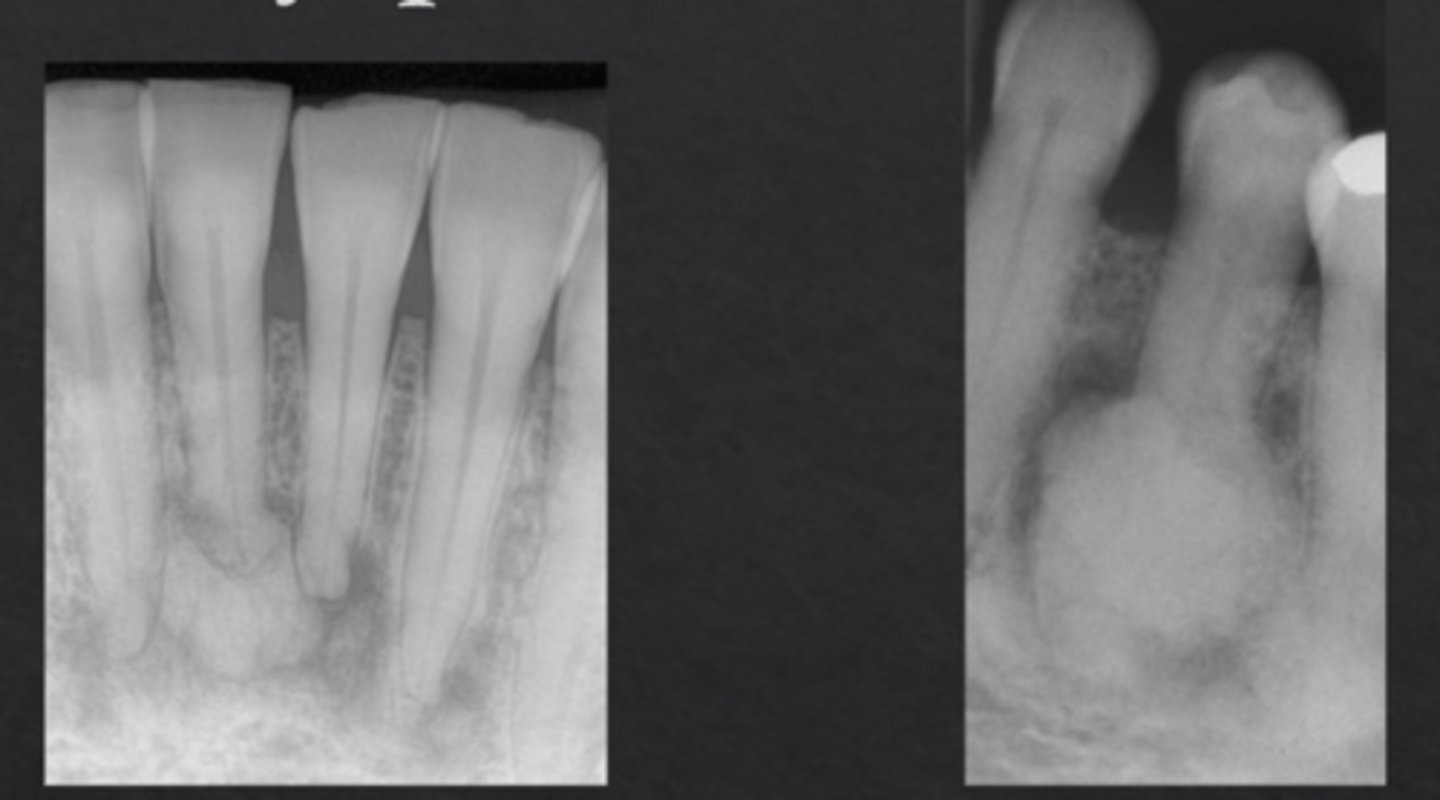

What is dens invaginatus (dens in dente)?

Infolding of enamel into the tooth, forming "tooth within a tooth"

Which tooth is most commonly affected by dens invaginatus?

Maxillary lateral incisors